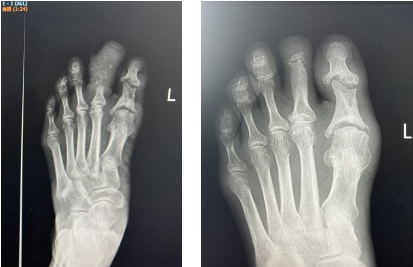

治療前后對比

3個多月后,趙阿姨回到醫(yī)院來拆掉外架,經(jīng)傷趾DR治療前后對比顯示,其左足第二趾血供明顯改善,創(chuàng)面完全愈合,傷趾還長出了新指甲,與之前腫脹、糜爛的足趾判若兩“趾”。

治療前后DR對比